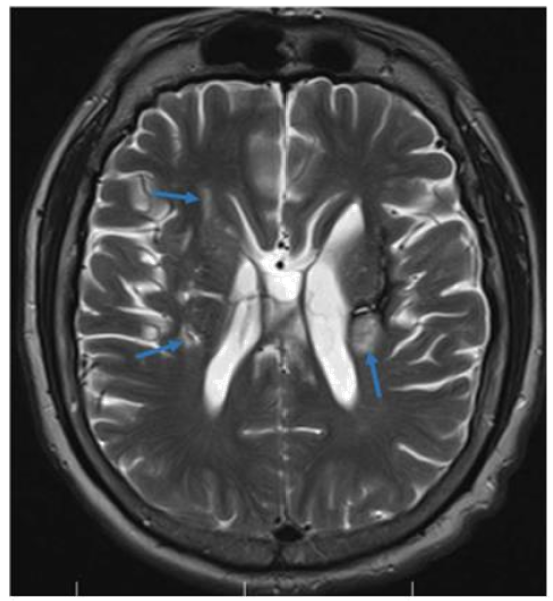

Soap Bubble Appearance: Dysembryoplastic Neuroepithelial Tumor “DNET”

Hajar Zebbakh, Abir Lemrabet, Hind Sahli, Siham El Haddad, Nazik Allali and Latifa Chat. 15(6): 23-24.